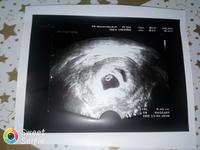

@hobbitka Já jsem v čekárně stála a jen se modlila: prosím ne dvojčata, jen ne dvojčata. Čekáme tedy jen jedno 😅

Jojo vzpomínám si na ten šok taky... prvně sotva jedno a najednou buch dvě 😀🤭 gratuluji

😅 Dvojité potěšení 😅